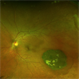

- https://imagebank.asrs.org/file/15894/retinal-detachment-right-eye-optomap See the previous submission above using an Optos TX 2000. Now, 12 years after his RD OD surgery, he remains attached. Comparatively one of the most amazing cases I've been privileged to be part of. This RD Repair from 2014 still going strong! Camera: Optos California